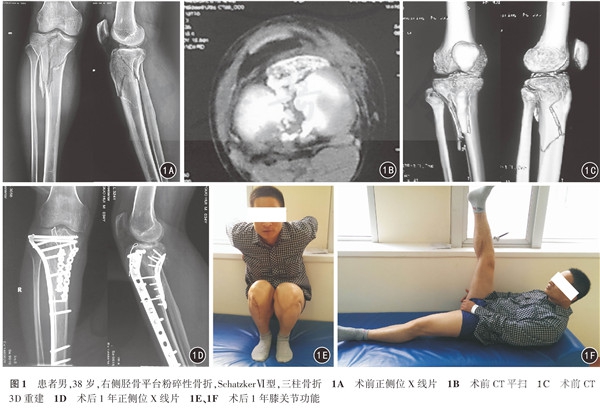

患者术后即刻和1年胫骨平台内翻角、后倾角的变化差异均无统计学意义(P值均>0.05)。见表1。术后1年的膝关节Rasmussen功能评分:优9例,良7例,可1例,差0例,总优良率16/17。典型病例见图1。